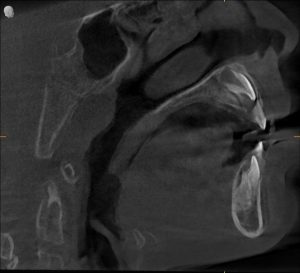

When Aarav visited the clinic, a comprehensive airway and dental evaluation told a different story.

Key Findings

- Narrow upper jaw (maxilla)

- High-arched palate

- Constricted airway space

- Improper tongue posture

- Chronic mouth breathing habit

The real issue wasn’t just adenoids — it was structure.

A narrow jaw meant less space for the nasal airway, forcing him to breathe through his mouth.